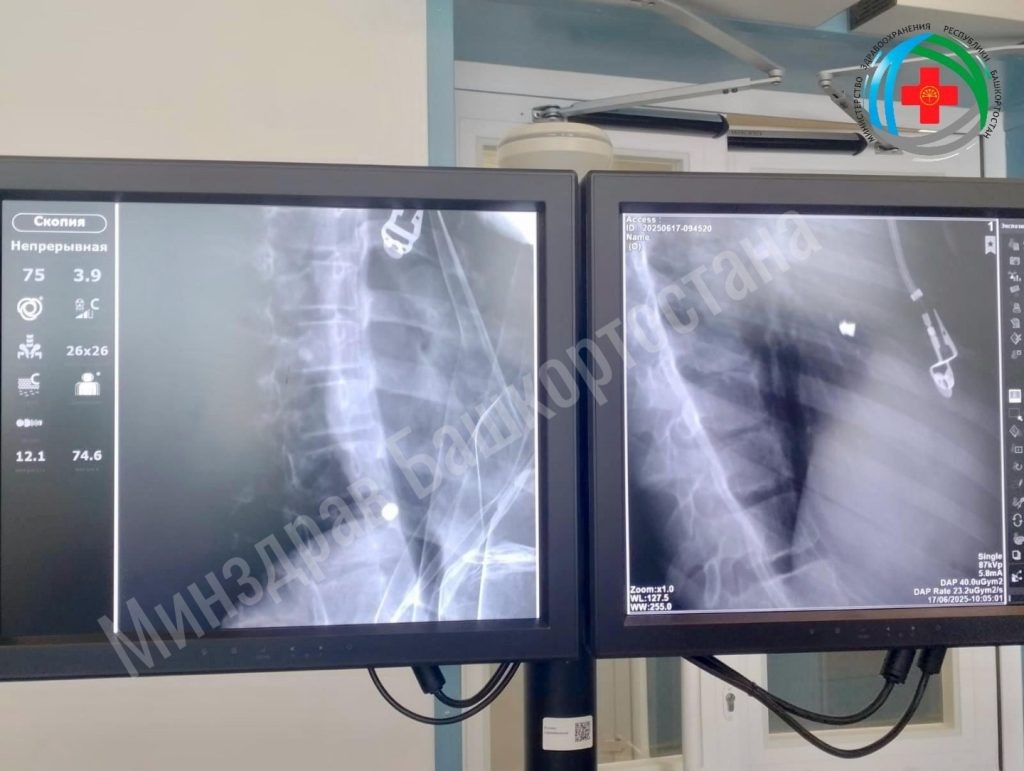

В Башкирии спасли 11-летнюю девочку с пулей в сердце. Об этом сообщил министр здравоохранения республики Айрат Рахматуллин. Операцию проводили совместно специалисты Республиканской детской клинической больницы и Республиканского кардиоцентра. Подросток получила ранение в результате несчастного случая. Инцидент с пневматическим оружием произошел в Иглинском районе. В РДКБ пациентка поступила в тяжелом состоянии. У нее были проникающее ранение сердца и травма легкого. Ей провели торакотомию – операцию по вскрытию грудной клетки и успешно извлекли пулю. Девочка находится в кардиоцентре. «МБ» писал, что в Башкирии спасли пациентку с огромной кистой.

В РДКБ пациентка поступила в тяжелом состоянии. У нее были проникающее ранение сердца и травма легкого. Ей провели торакотомию – операцию по вскрытию грудной клетки и успешно извлекли пулю. Девочка находится в кардиоцентре.